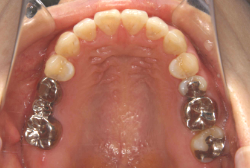

診断の結果、典型的なアングル2級1類の上顎前突です。上下歯列の正中の不一致も見られます。しかし、歯の大きさは平均値に近く、配列の凸凹がそれほど見られません。このまま放置すると、将来的には抜歯を伴う矯正治療を行う可能性が高くなりますが、このタイミングで適切な治療をすると、非抜歯治療が可能かもしれません。

矯正歯科医が着目するのは、奥歯の噛み合わせの位置関係です。前歯の位置にそれなりの差が生じていても、奥歯の位置が正しければそれほど重症という評価にはなりません。このケースの場合は、上下の第一大臼歯の位置関係は、直線的に一致しているタイプでした(矢印が一致)。混合歯列時期の奥歯の位置関係としては、ほぼ正常な状態といえますが、症状から言うと、上の奥歯をもっと後ろに下げてやることができれば、上顎歯列全体に余裕ができるので、凸凹も解消できるし、前歯の傾きを内向きに修正することもできると考えられました。しかしこのまま全体に永久歯が生えきってしまうと、上の前歯が出たままになってしまいますので、生え替わりが完了する前に大急ぎで奥歯を後ろに下げる必要があると判断しました。

こういう症状でもっとも効果があるのが、顎外固定装置と言って、お口の外部から奥歯に力をかける方法です。 写真の装置はネックバンドというタイプの装置です。この装置は取り外し式ですので、夜寝るときに毎日自分で取り付けて、寝ている間に少しずつ上の奥歯を後ろに下げていきます。この装置には、奥歯を後ろに下げる効果だけでなく、上顎の過剰な成長発育の抑制、下顎の成長促進作用があるとされており、上顎前突の症状にはいずれも有利な効果が期待できます。

ネックバンドを1年半使用して、上顎大臼歯が十分後ろに下がったところで、裏側にリンガルアーチという固定のワイヤーを取り付けて、新しく生じた隙間が狭くならないよう「保隙(ほげき)」という処置をして、永久歯が生えそろうまで待機中の様子です。配列全体に隙間が生じているのがお分かりいただけると思います。これだけの隙間が確保できていれば、抜歯をしなくても、あとで上の前歯を内側に理想的な角度で引っ込めることができます。このように完全に永久歯列になる前に、十分な隙間が確保できるかどうかが、非抜歯で矯正できるかどうかの分かれ目になります。

初診時と違い、上の奥歯がより後方に下がっていることが分かります。ただしこの段階では奥歯は後ろに下がりすぎの状態です。しかし次の段階でマルチブラケット法を始めると、上の奥歯は次第に前にズレて来ます。最終段階で正しい位置にするためには、この段階では余分に後ろに下がっている必要があります。

第2段階としてマルチブラケット法を非抜歯で1年間行いました。歯の傾斜が修正され、正中も一致し、美しく機能的な配列に仕上がりました。再診時に確保した隙間をすべて使って、すべての永久歯を理想的な位置に配列することができました。前傾していた上の前歯は真っ直ぐに直立し、完全な正常咬合が確立できています。